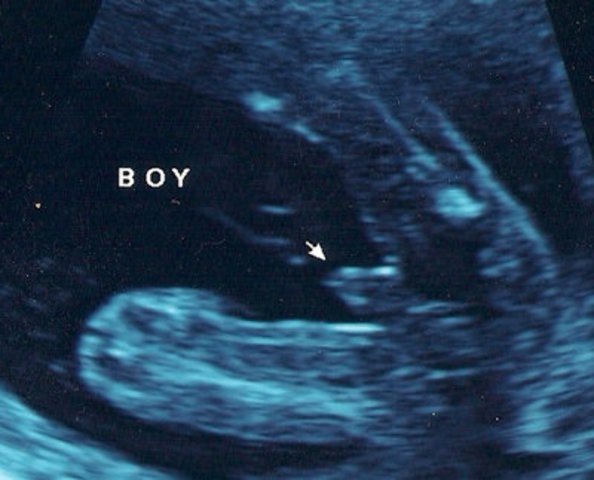

• Prenatal- Sex Determined

Prenatal- Sex Determined

The sex is determined is between 8 and 24 weeks. There is a hormone that is released that either causes the development of male or female genitals. This is shown to us our book on page 73. Then a mother can be able to see if their unborn child is a boy or a girl. This ultrasound picture shows that this is a boy.

Image taken from Google images